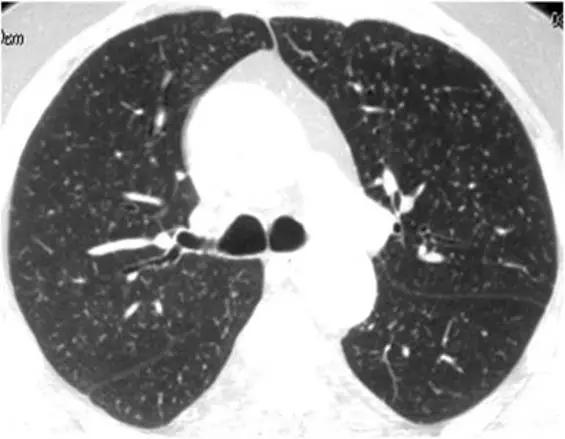

HRCT上的磨玻璃样改变被定义为不透明的薄雾影增加,并保留了支气管和血管标记。经典疾病:亚急性过敏性肺炎(HP),其特征是磨玻璃样混浊的对称斑片或弥散性双侧区域,伴有边界义不清的小叶中心型结节。有助于将亚急性HP与其他相似疾病分开的特征是,在吸气图像和气管呼气图像上,小叶区域的衰减和多血管影。磨玻璃样的最常见的鉴别疾病是呼吸性毛细支气管炎相关的间质性肺病(RB-ILD)、脱屑性间质性肺炎(DIP)和肺囊虫性肺炎。

*亚急性过敏性肺炎。 HRCT显示“磨玻璃样”改变,有少量小叶结构,没有纤维化改变

RB-ILD可表现为中度到广泛性的双侧磨玻璃影,边界不清的小叶中心型结节,支气管壁增厚。有时,在肺基部可能会出现轻微的网状结构。区分RBILD和亚急性HP的线索是RB-ILD存在上叶轻度肺气肿,HP吸烟者存在吸烟习惯的改变。

*RB-ILD 上叶水平的HRCT显示弥散的“毛玻璃样”,小叶透亮区代表伴随的小叶肺气肿。